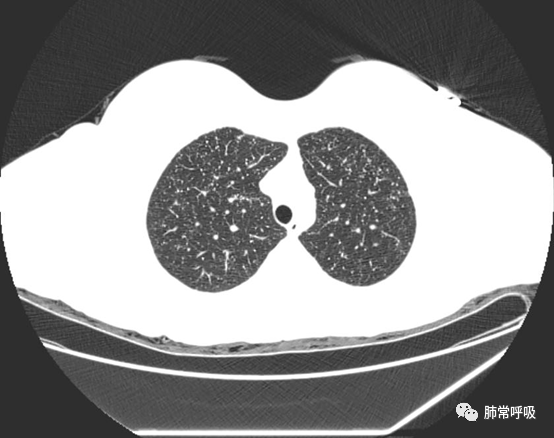

胸部ct初次发现肺部结节如何处理_体检_人群_检查